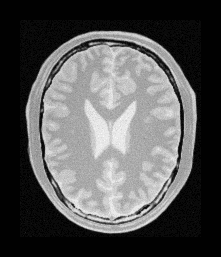

To me that looks like a successful registration. Can you elaborate why this is not a good result?

It is not as good as (has obvious rotation in result image) the one shown in your example: https://github.com/SuperElastix/SimpleElastix/blob/develop/Documentation/Sphinx/AffineRegistration.rst